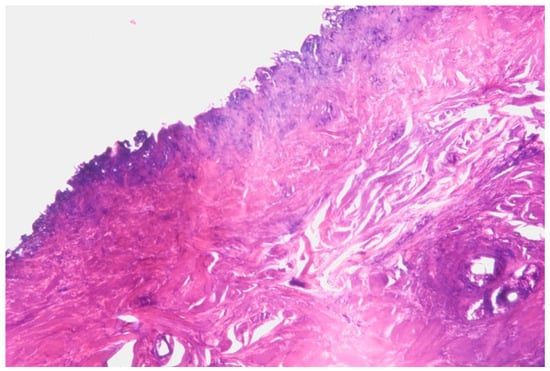

3.1.4. Clinical Case 4: Skin Dissection Area, Scalpel Incision (See Figure 5)

Description: No necrotic changes were noted, the vessels were dilated and congested, and there were extensive hemorrhages at the resection margins.

Figure 5.

Skin changes following scalpel incision. H&E staining, 10× objective magnification.